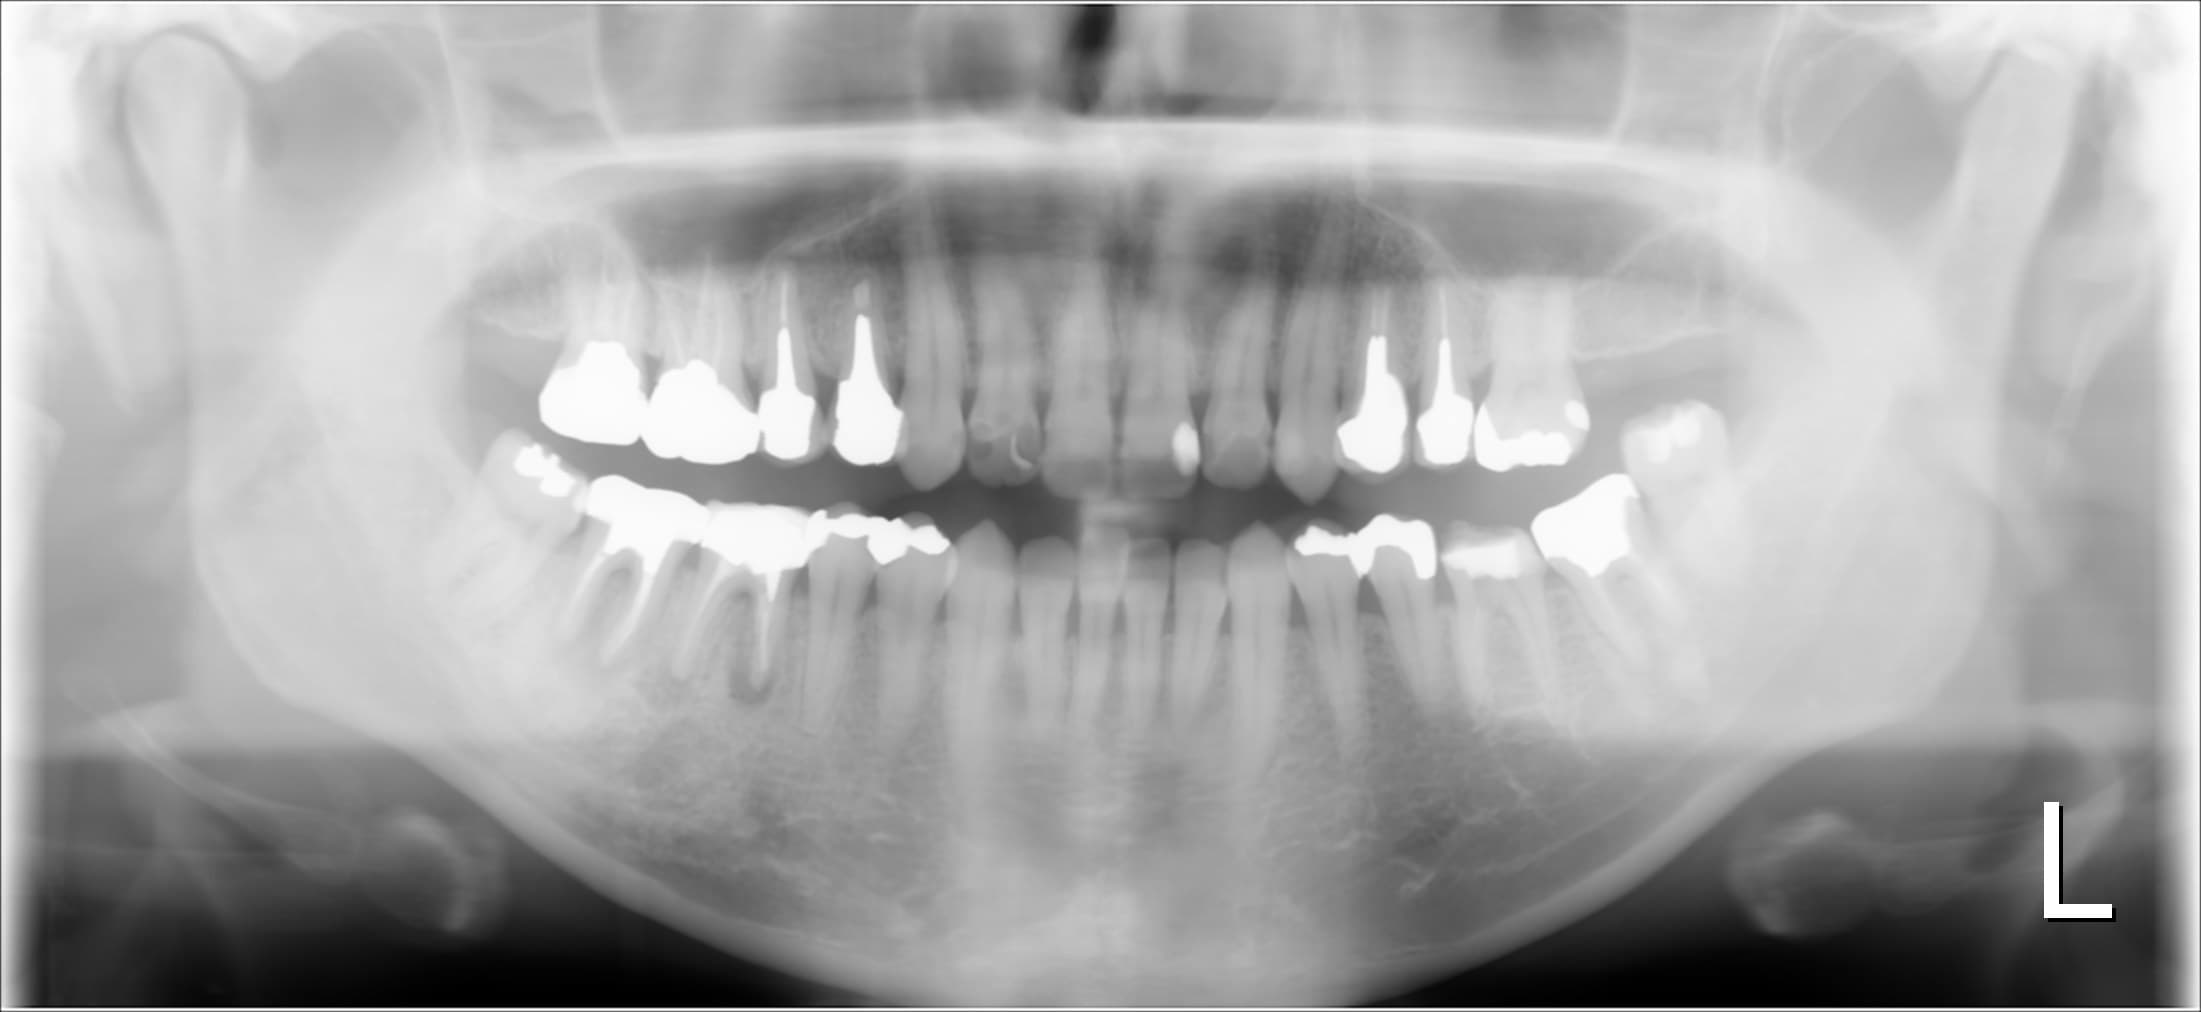

相談の結果、他にも色々と治療が必要な場所があり、時間はかかりますが、ご家族の協力の元、専門根管治療で一つずつ治していくことになりました。

根の治療である根管治療をしっかり成功させていくには、インプラント治療と同様に、歯周病が管理された清潔な口腔内環境であることも重要な要素となってきます。

今回も実際に歯周病菌にも感染しており、ご自身でも自覚があった為、歯周病の原因と治療法についてお伝えし歯周専門治療を行うこととしました。